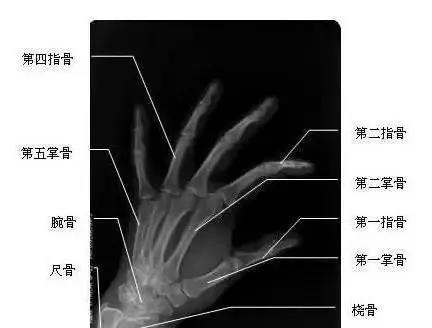

我們先來看一下雙手漂亮的“骨感”圖,這是雙手主要骨頭組成部分。骨頭外面覆蓋了肌肉、血管、神經(jīng)、筋膜、皮膚等組織。腱鞘,就是指纖維鞘+指滑膜鞘的雙層套管樣結(jié)構(gòu),對(duì)肌肉的肌腱起約束、支持和滑車等作用。所謂腱鞘炎,就是指肌腱及其周圍覆蓋組織發(fā)生炎癥。腱鞘炎最常發(fā)生于手部或腕部,但也可發(fā)生于身體其他部位,如踝部。